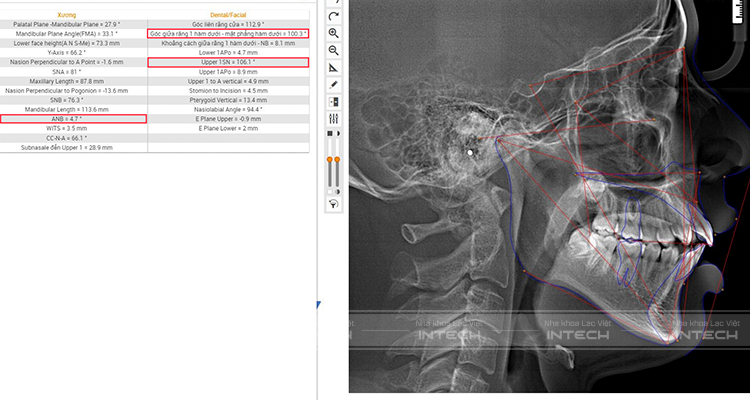

Phân tích phim sọ nghiêng

Chỉ số trên phim sọ nghiêng

- Chỉ số ANB (chỉ số đánh giá tương quan trước sau của hàm trên và hàm dưới) = 4,7 so với tiêu chuẩn = 2 - 4,5

- Chỉ số chụp răng cửa hàm trên 106,1 độ, trong khi đó tiêu chuẩn = 98 - 106 độ

- Trục răng cửa hàm dưới bình thường là 100,3 độ, tiêu chuẩn là 90 độ dẫn đến trục răng cửa hàm trên hàm dưới đang có độ chìa lớn so với tiêu chuẩn.